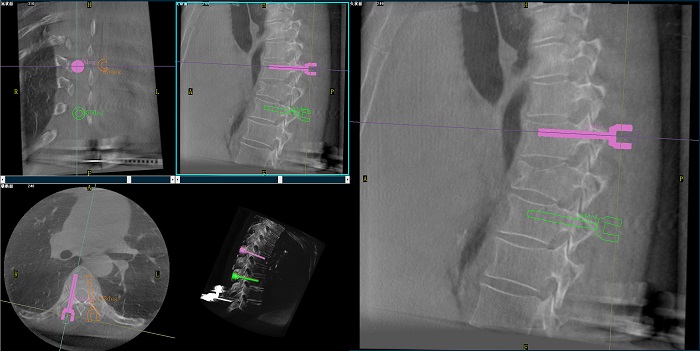

②機器人輔助胸椎手術操作難點之路徑規劃

人體胸椎的椎弓根較腰椎更狹窄,周圍有重要的神經和血管,選擇合適尺寸和長度的螺釘至關重要。螺釘過粗可能損傷椎弓根,過細容易發生形變,固定強度不夠;螺釘過長可能穿透椎體前緣,造成損傷,過短則固定不牢。

使用機器人輔助手術,醫生不僅可以在影像的引導下,一次性完成多枚螺釘的路徑規劃,提高手術效率,而且可以精確地選擇螺釘的角度、直徑和長度,提高手術的成功率。

③機器人輔助胸椎手術操作難點之精準置釘

普愛醫療骨科手術機器人的高精度機械臂,按照規劃好的路徑及角度,自動精準定位穿刺點,醫生打入克氏針后,正側位圖像顯示精度滿足預期,醫生完成置釘等后續手術操作。